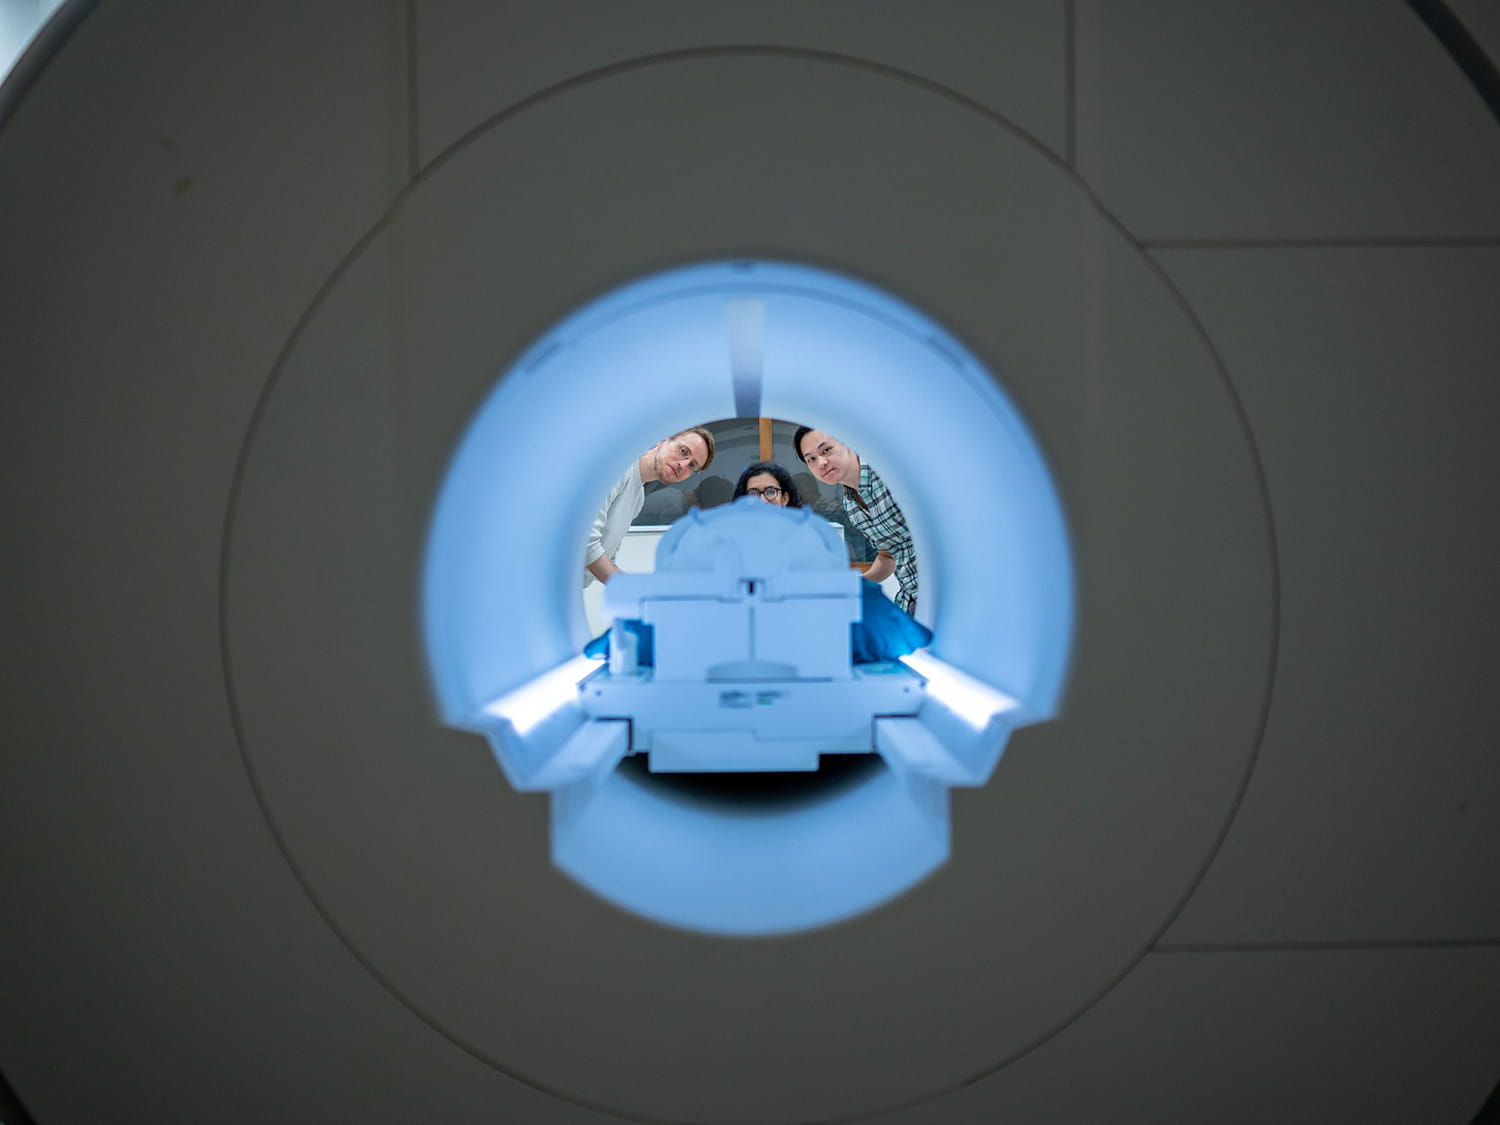

Il faut dire qu'Iseult est équipé d'un champ magnétique de 11,7 teslas, rapporte le Commissariat à l'énergie atomique. Cette information ne vous parle pas ? Sachez que si vous vous rendez demain dans un hôpital pour faire une IRM, vous n'aurez affaire qu'à des machines dotées de 1,5, voire 3 teslas. Iseult est ainsi quatre à six fois plus puissant qu'un appareil d'IRM lambda. Sur son site, le CEA annonçait en 2017 qu'il avait pour vocation d'obtenir des images du cerveau "100 fois plus précises" qu'avec les imageurs classiques. Pour parvenir à ces 11,7 teslas, Iseult est composé d'un énorme aimant de cinq mètres de long, pesant pas moins de 130 tonnes, qui a été fabriqué à Belfort entre 2010 et 2017, et alimenté d'un courant d'une très grande intensité (environ 1 500 ampères).

Installé à NeuroSpin, le centre CEA de Paris-Saclay (Essonne) en 2017, Iseult n'avait pu être mis en exploitation qu'en 2021, avec de premières images livrées au mois d'octobre de la même année. À l'époque, un potimarron avait servi de cobaye, de nombreux réglages et autorisations devant encore être acquis pour pouvoir faire appel à des êtres humains. "En gagnant en résolution et en contraste, on peut avoir des détails époustouflants sur les détails anatomiques, comme des veines, inatteignables à plus bas champ magnétique", exposait ce mardi Nicolas Boulant, le directeur de recherche au Commissariat à l'énergie atomique (CEA), dont Le Parisien se fait l'écho.